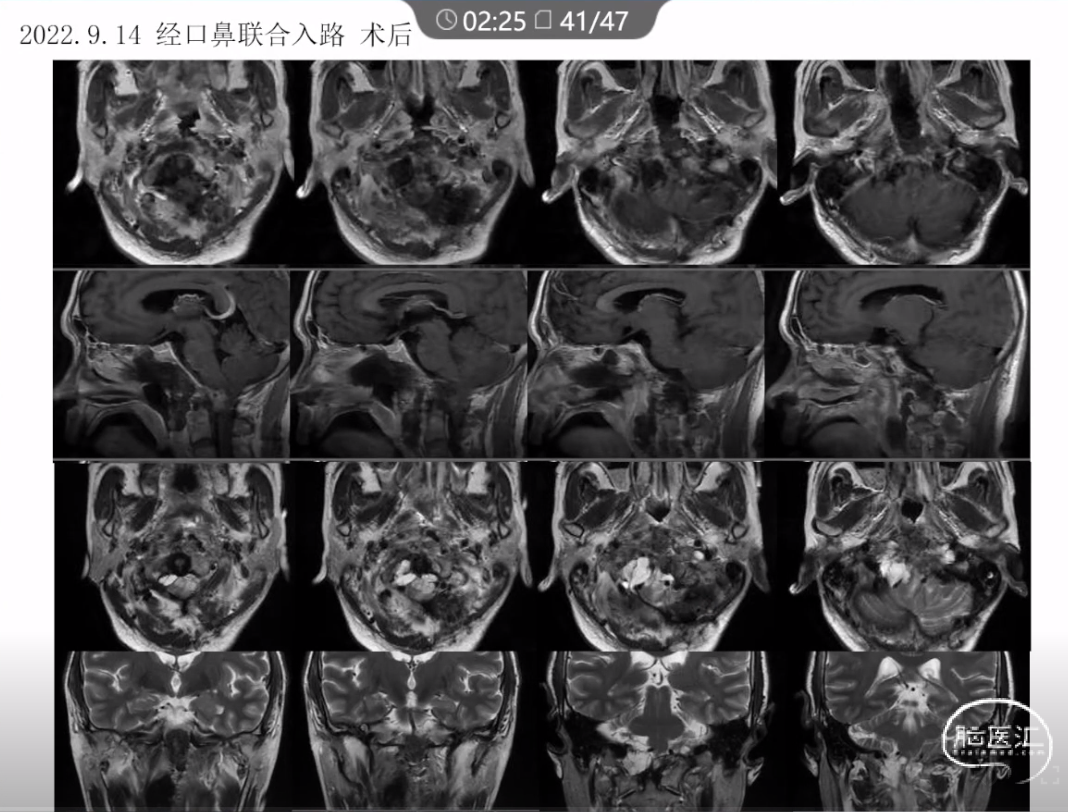

本文主要内容为:脊索瘤临床特点、治疗选择,以及多个手术病例。